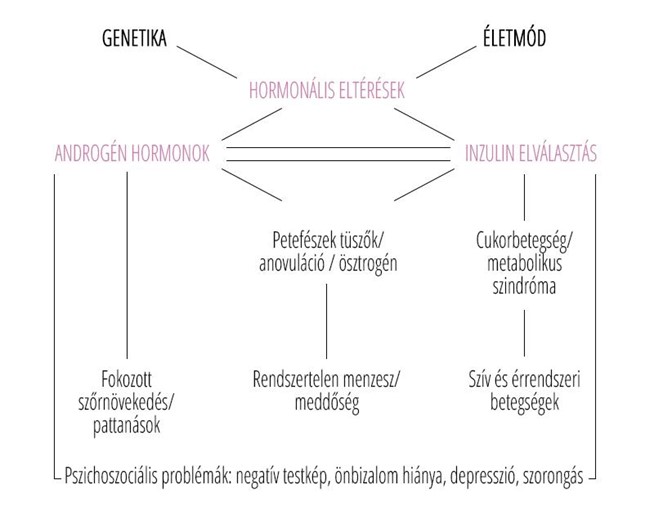

Az edukáció olyan fontos kérdéseket érint, mint: mi számít meddőségnek, mikor érdemes szakemberhez fordulni, hogyan hat az életkor a termékenységre, illetve milyen kockázatot jelentenek a szexuális úton terjedő fertőzések. Az iránymutatás külön kitér a legfontosabb kockázati tényezőkre, mint a dohányzás, a túlzott alkoholfogyasztás, az elhízás vagy éppen az alultápláltság, melyek mind kedvezőtlenül hathatnak a reproduktív egészségre. Ezzel szemben a kiegyensúlyozott, tápanyagokban gazdag étrend, a rendszeres testmozgás, valamint a dohányzás elhagyása bizonyítottan hozzájárulhat a termékenység megőrzéséhez és a későbbi problémák megelőzéséhez.